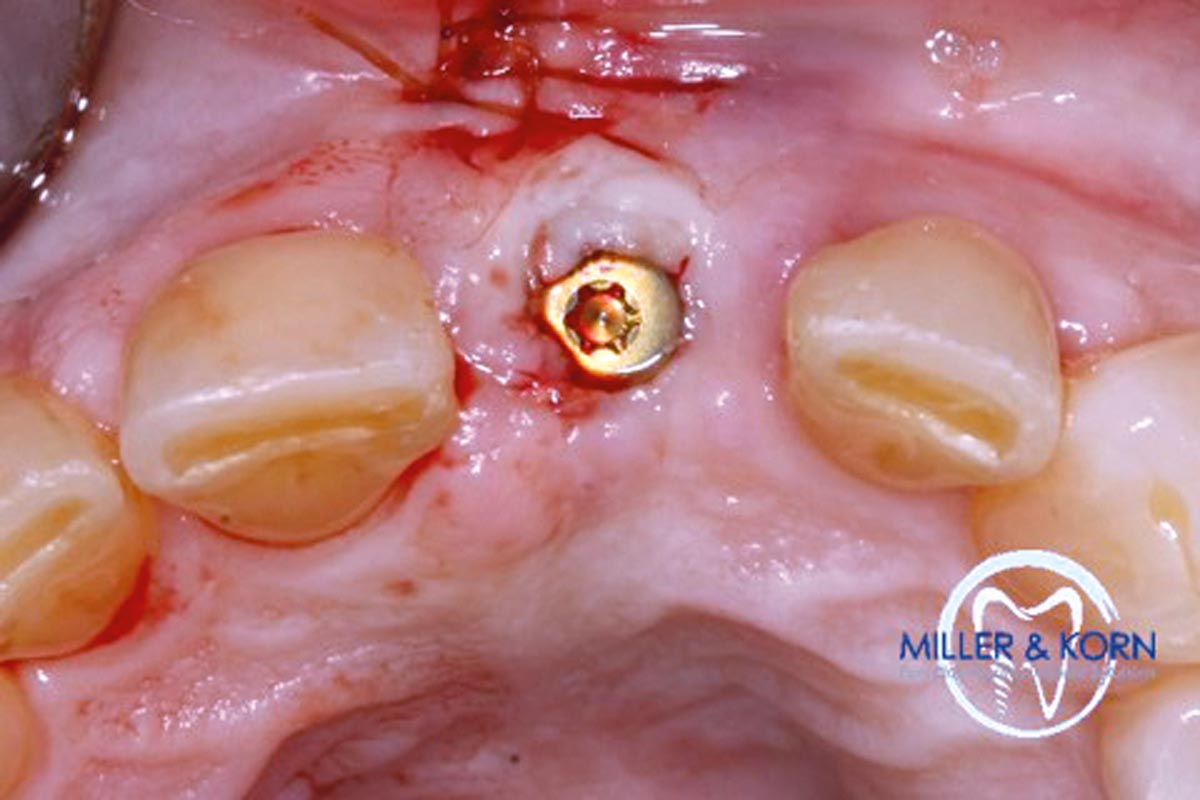

30/39 - Placed healing abutmentImmediate implant placement and correction of horizontal and vertical bone loss using an allograft bone ring, cerabone® and Jason® membrane - Drs. Miller and Korn